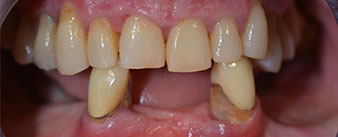

La paziente, 64 anni, presenta una dentatura residua di denti 38, 33 e 43 e una protesi combinata innestata nella mandibola (Fig. 1 e 2).